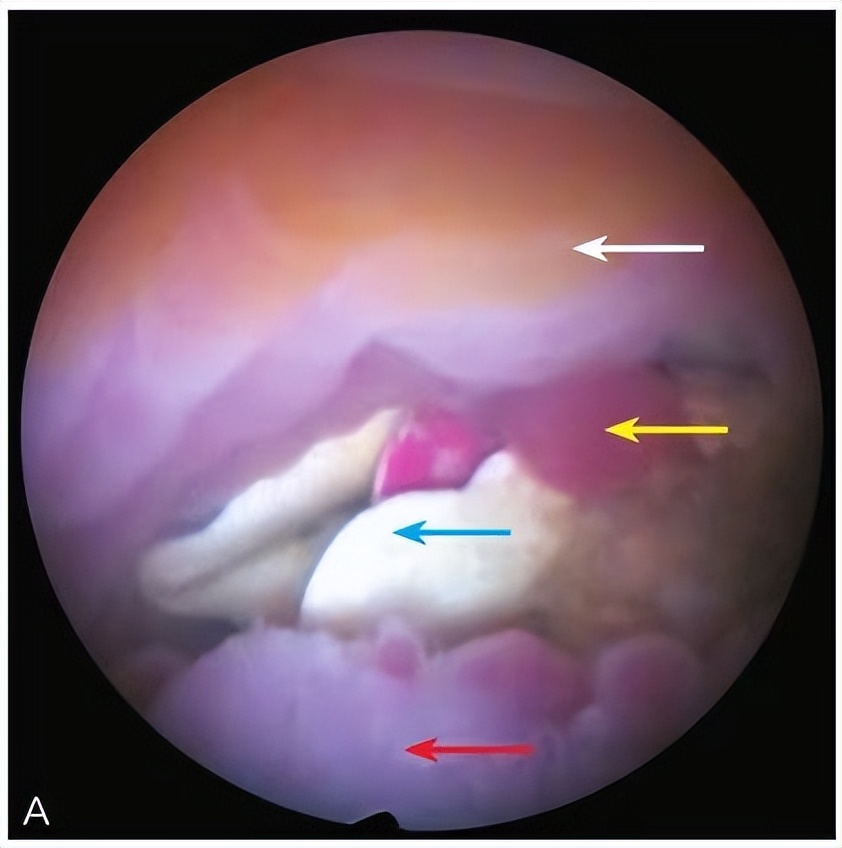

1)宫腔残留、宫内节育器异位或嵌顿、宫腔及阴道内异物的定位和取出;

*女幼**阴道异物

子宫黏膜下肌瘤